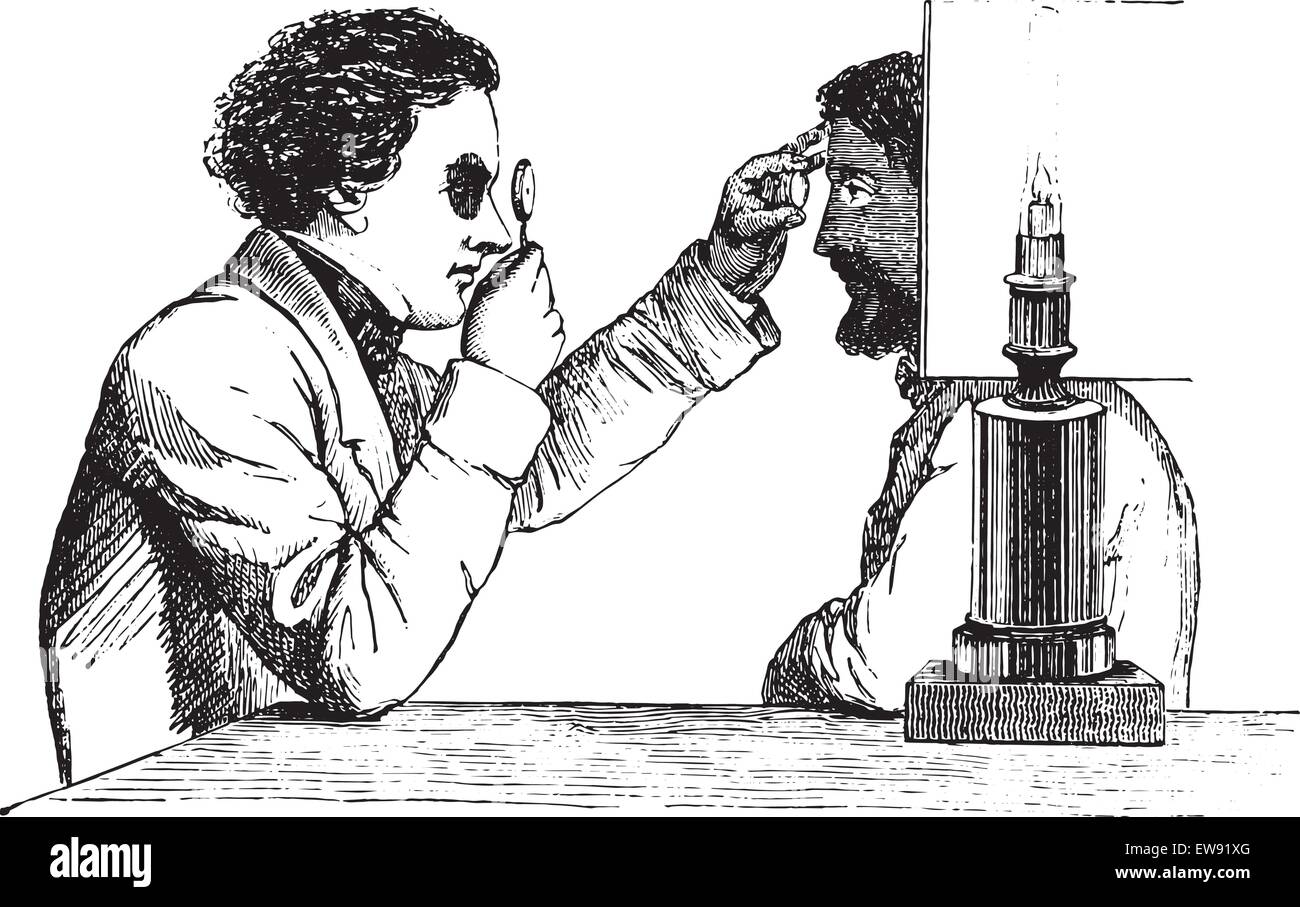

Engraving depicting an ophthalmoscope in use. Ophthalmoscopy, also called funduscopy, is a test that allows a health professional to see inside the fundus of the eye and other structures. The ophthalmoscope was invented by Hermann von Helmholtz (1821-1894) a German physician and physicist. Dated 19th century Stock Photohttps://www.alamy.com/image-license-details/?v=1https://www.alamy.com/engraving-depicting-an-ophthalmoscope-in-use-ophthalmoscopy-also-called-funduscopy-is-a-test-that-allows-a-health-professional-to-see-inside-the-fundus-of-the-eye-and-other-structures-the-ophthalmoscope-was-invented-by-hermann-von-helmholtz-1821-1894-a-german-physician-and-physicist-dated-19th-century-image186347727.html

Engraving depicting an ophthalmoscope in use. Ophthalmoscopy, also called funduscopy, is a test that allows a health professional to see inside the fundus of the eye and other structures. The ophthalmoscope was invented by Hermann von Helmholtz (1821-1894) a German physician and physicist. Dated 19th century Stock Photohttps://www.alamy.com/image-license-details/?v=1https://www.alamy.com/engraving-depicting-an-ophthalmoscope-in-use-ophthalmoscopy-also-called-funduscopy-is-a-test-that-allows-a-health-professional-to-see-inside-the-fundus-of-the-eye-and-other-structures-the-ophthalmoscope-was-invented-by-hermann-von-helmholtz-1821-1894-a-german-physician-and-physicist-dated-19th-century-image186347727.htmlRMMR4TBY–Engraving depicting an ophthalmoscope in use. Ophthalmoscopy, also called funduscopy, is a test that allows a health professional to see inside the fundus of the eye and other structures. The ophthalmoscope was invented by Hermann von Helmholtz (1821-1894) a German physician and physicist. Dated 19th century